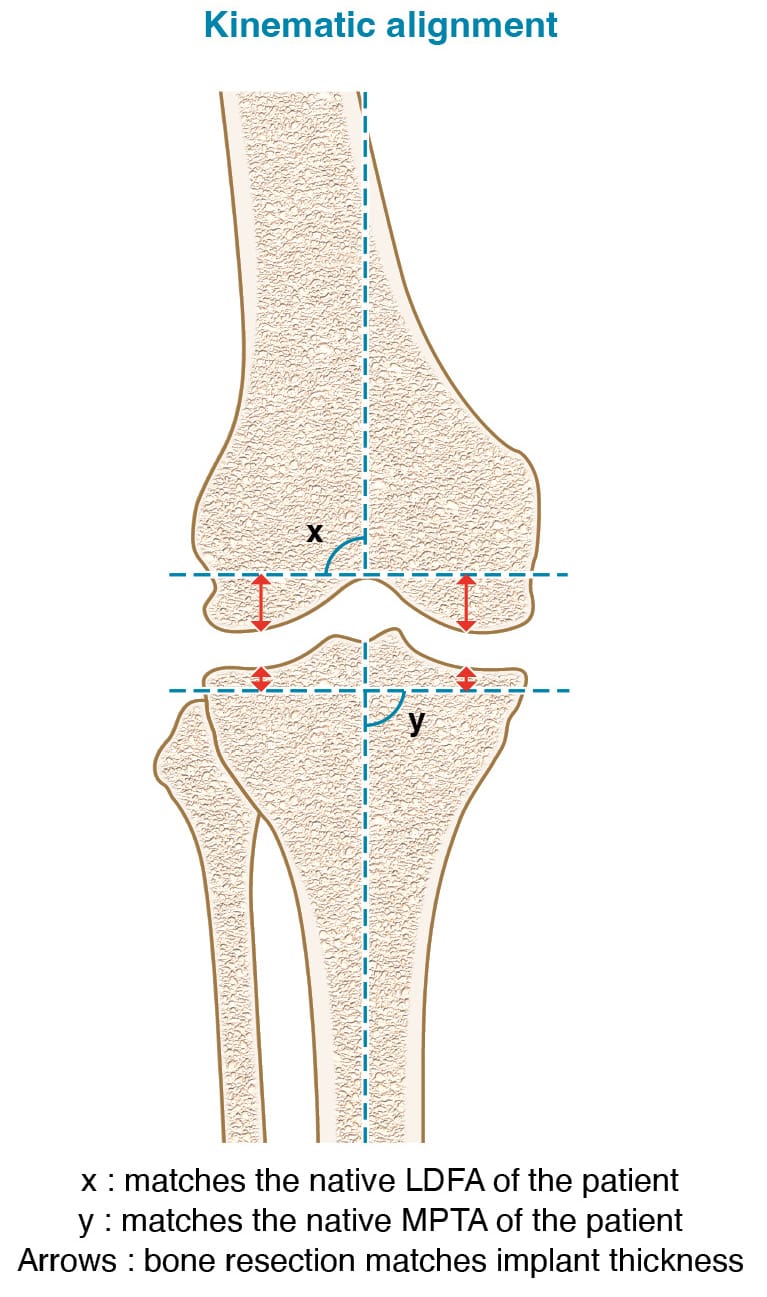

Kinematic alignment (KA) represents the pinnacle of achieving perfect gap balancing with bone cuts. Howell, in 2014, described this method with the goal of restoring the patient’s pre-arthritic knee anatomy through precise femoral and tibial cuts, thereby obviating the need for ligament release [6] Howell SM, Roth JD, Hull ML. Kinematic Alignment in Total Knee Arthroplasty 2014:10.. The femoral distal cut is tailored to the patient’s LDFA, while the tibial proximal cut matches the patient’s MPTA. Using “calipered instrumentation,” Howell’s technique measures resected bone to ensure the prosthetic components fit perfectly into the created gap. (Figure 5) This technique is the most conservative for the anatomy of the patient however it could lead to recreate patho-anatomy and reproducing poorly aligned lower limbs.